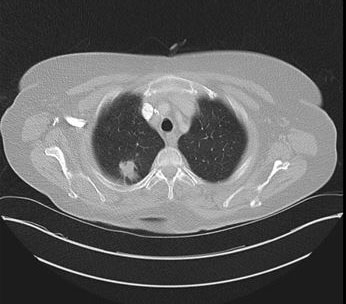

A completion CT brain/chest/abdomen was ordered which showed a lesion in right upper lobe apical segment which measures about 26 × 20 mm × 32 mm consistent with lung cancer (Figure 2). There were also hepatic, splenic, intracranial, multiple axial skeletal metastases.

Figure 2: Completion CT chest showing lung cancer.